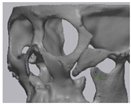

2.5. Cone Beam CT and 3D Comparison

3.2. Fusion Rate Analysis Using 3D CT

3.3. 3D Comparison between Immediate Post Operative and 6 Months Post Operative